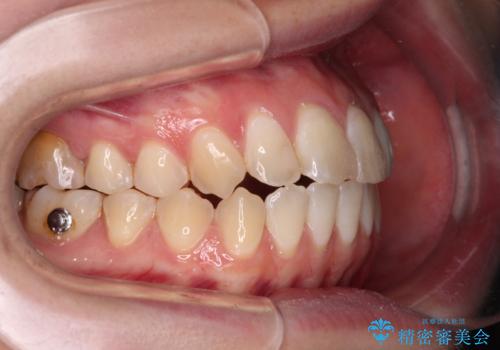

開咬を治す インビザラインによる矯正治療

- 上下前歯の開咬を気にして来院された患者様です。

開咬はインビザラインを用いると有意に改善ができるため、インビザラインによる矯正治療を行うこととしました。

途中1年8ヶ月ほど来院されず、久しぶりの来院後は治療が面倒とのことで、前歯の叢生や隙間に不十分な点が残った状態での終了となりました。